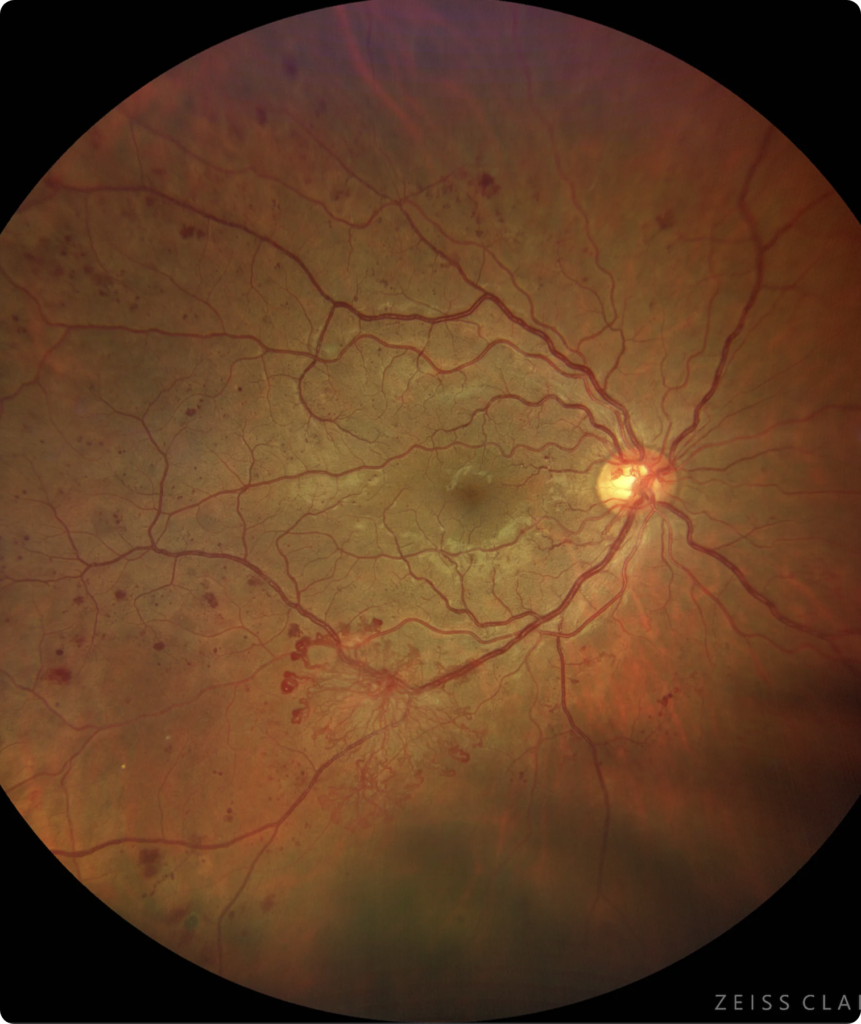

Sin embargo después de varios años de padecer la enfermedad (5 a 10 años, dependiendo de qué tan elevados son los niveles de glucosa y de la predisposición de cada paciente), empiezan a aparecer los primeros datos de retinopatía diabética no proliferativa (pequeños aneurismas y hemorragias en la retina), que no causan problemas en la visión, y son sólo evidentes a la revisión oftalmológica.

A medida que avanza el tiempo y no se controlen los niveles de glucosa, las lesiones en la retina aumentan en número e intensidad, como puede apreciarse en la fotografía. Aún en esta etapa donde hay muchas lesiones, la visión del paciente puede estar intacta.